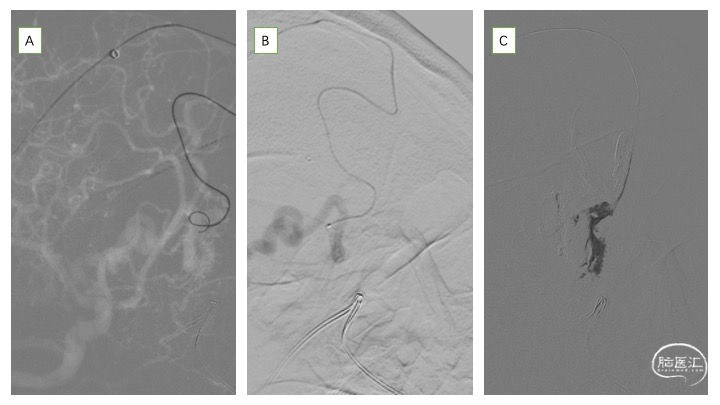

详细分析患者瘘口的血管构筑学(图3),术者认为经静脉途径的优势在于:相对于动脉途径,微导管经静脉途径能够确切地到达瘘口。且该患者的引流虽经皮层及额底内侧静脉分别向矢状窦及直窦引流,但两支引流静脉均起源于一短段的引流静脉。虽然皮层引流静脉有两处走行纤细,但根据术者既往的经验,微导管通过此处并不十分困难。术中同时穿刺右侧股动脉及股静脉,将造影导管超选至右侧颈总动脉,用于实时造影、三维血管构筑分析及路图指导。同时,将Neuronmax长鞘引导至右侧横窦,6F银蛇中间导管引导至上矢状窦中份。在路图指导下,Echelon-10导管经由矢状窦-右侧额叶皮层静脉途径成功超选至右侧额底引流静脉开口,在此处放置弹簧圈,用于防止Onyx逃逸,导致静脉窦栓塞或肺栓塞,随后在静脉端使用逆向高压锅技术,注入Onyx胶,完全栓塞瘘口(图4、5)。

栓塞术后即刻CT未见颅内出血、Onyx胶逃逸或异位栓塞(图6)。次日,患者未诉明显不适,查体无新发神经系统体征。术后第二日,患者顺利出院。